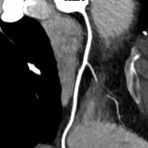

• Darstellung der Blutgefäße (sog. CT- Angiographie)

• Darstellung der großen Gefäße zur Erkennung von Gefäßverschlüssen (z. B. Mesenterial - Arterienembolie oder Einengungen von Gefäßen (z. B. Nierenarterien)

• Darstellung und Therapieplanung von Aneurysmen (CT- Angiographie)

• mehrdimensionale Darstellung vasculärer Strukturen mit zahlreichen Auswertungstools